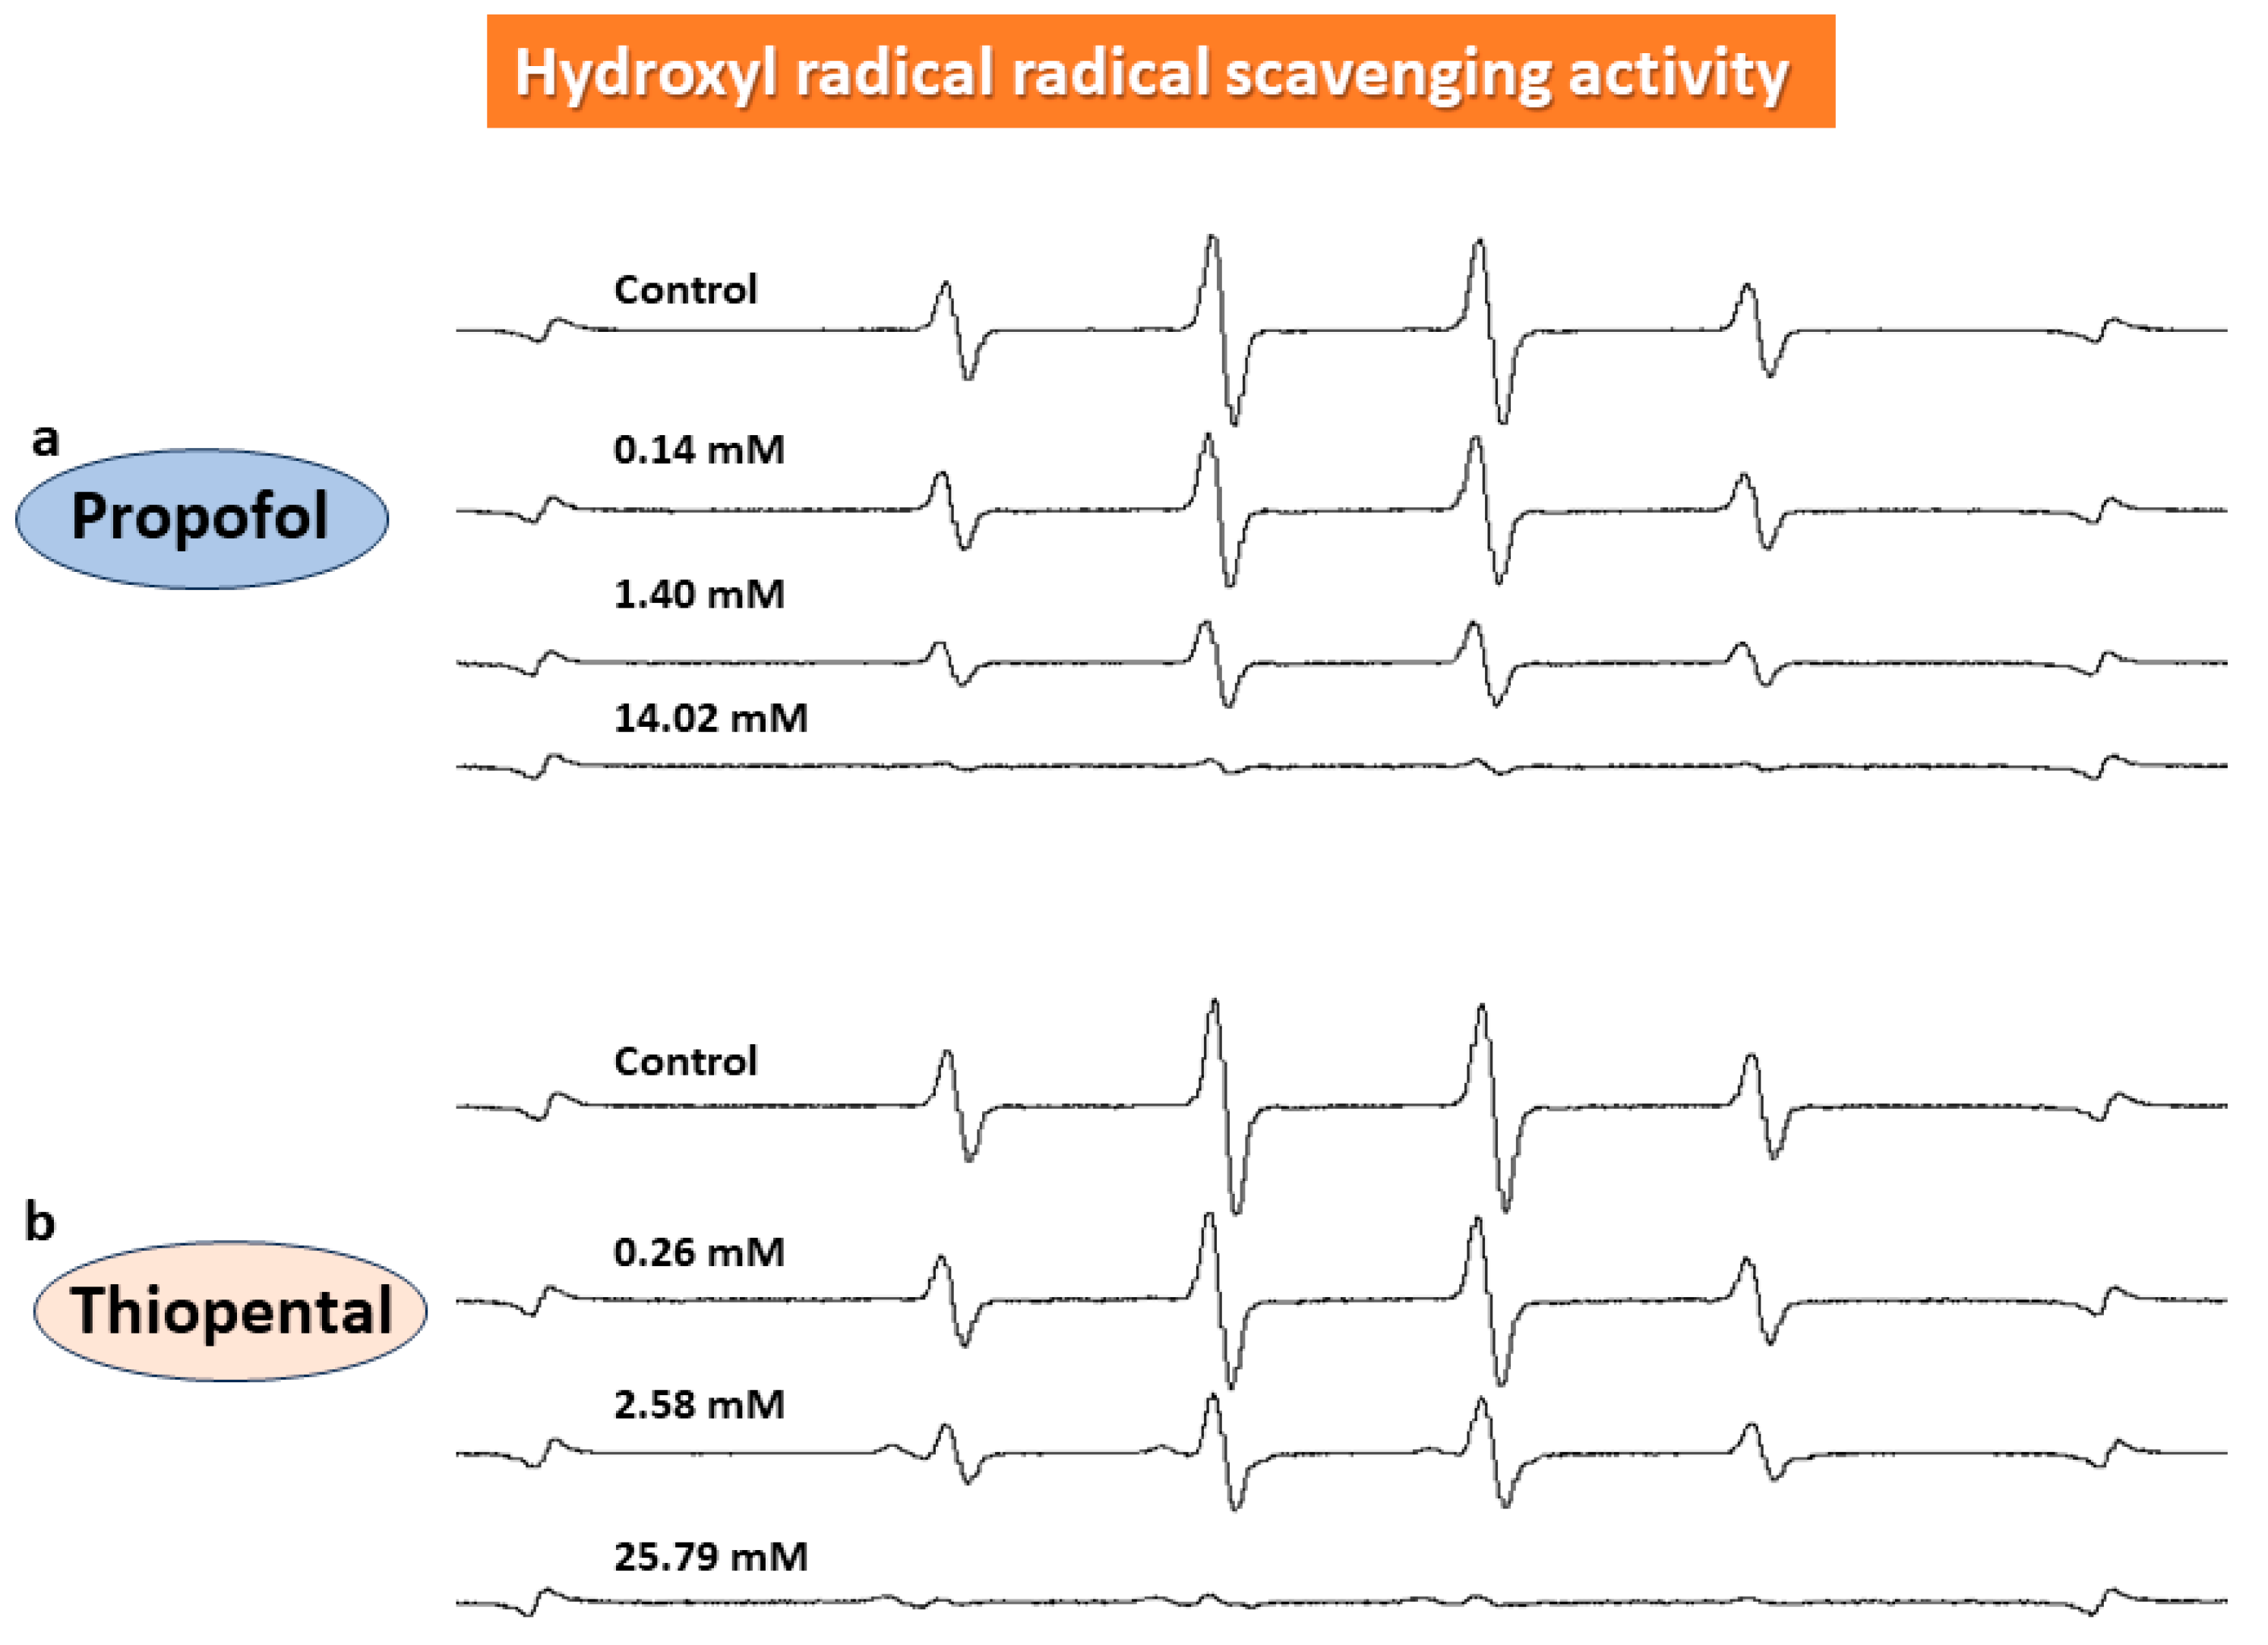

2.2. In Vitro ESR Method

3. Results